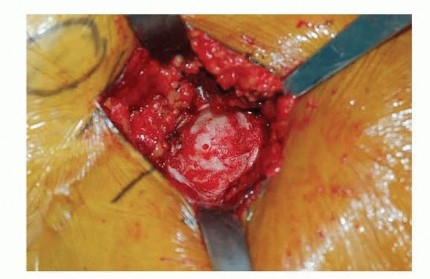

صورة طبية: نصف مفصل الورك: دليلك الشامل لدواعي الاستخدام والأنواع في صنعاء